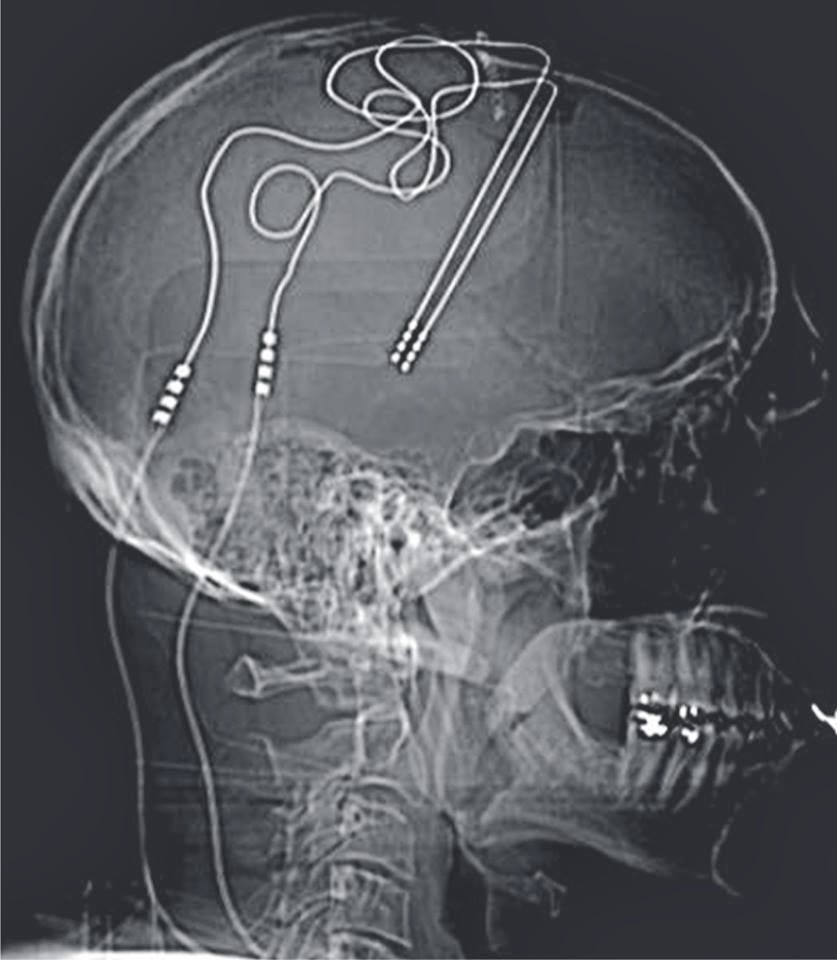

Снимки мастерства

Интероцептивные ощущения: Понимание внутреннего восприятия